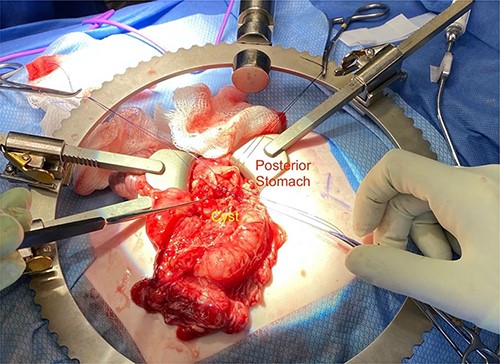

Given the location of the cyst, we felt resection would require a pancreaticoduodenectomy. Alternatively, because there was no biliary obstruction or evidence of chronic/recurring pancreatitis, it was safer to internalize the duplication cyst. The anterior cyst wall was opened, and its contents were about 2 ml of clear white fluid and a small amount of white mucous debris; samples were sent for culture and lipase, but unfortunately the amount of sample was not adequate for lipase. A mucosectomy (to mitigate the long-term risk of malignant transformation) and cystgastrostomy to the posterior antral wall were performed (Fig. 4). A Penrose drain was placed across the cystgastrostomy to maintain patency (Fig. 5).

Penrose drain fixed across the cystgastrostomy with PDS sutures.